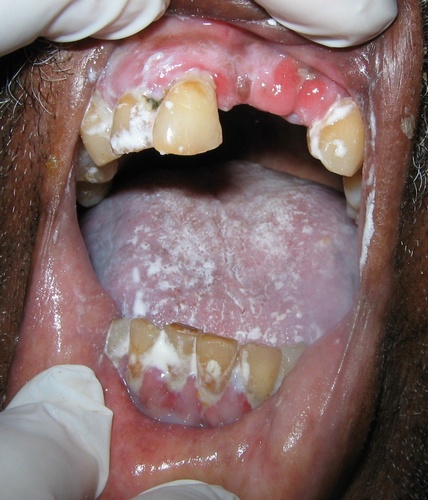

As fotos que ilustram esta matéria mostram bem a necessidade de que tanto falamos, são incontáveis cidadãos brasileiros: crianças, jovens, adultos, muitos deficientes, com problemas renais, cardíacos, mentais, com câncer, entre outras graves doenças; ricos, pobres, de todas as cores e raças que hoje se encontram internados em um hospital completamente dependentes e limitados, sem condições, na maioria das vezes, de falar nem mesmo de seus incômodos e de suas dores, muitos entubados e inconscientes.